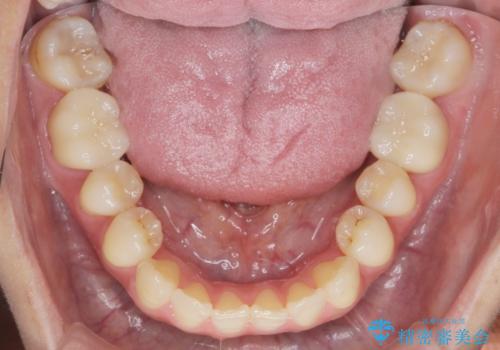

銀歯をゼロに! 短期間で行うメタルフリー治療

銀歯を丁寧に除去したのち、精度の良いセラミックインレー、セラミッククラウンで修復・補綴処置を行っていきます。

「長年気になっていた銀歯を全て除去し、気持ちが明るくなりました。」、と嬉しい感想をいただくことができました。